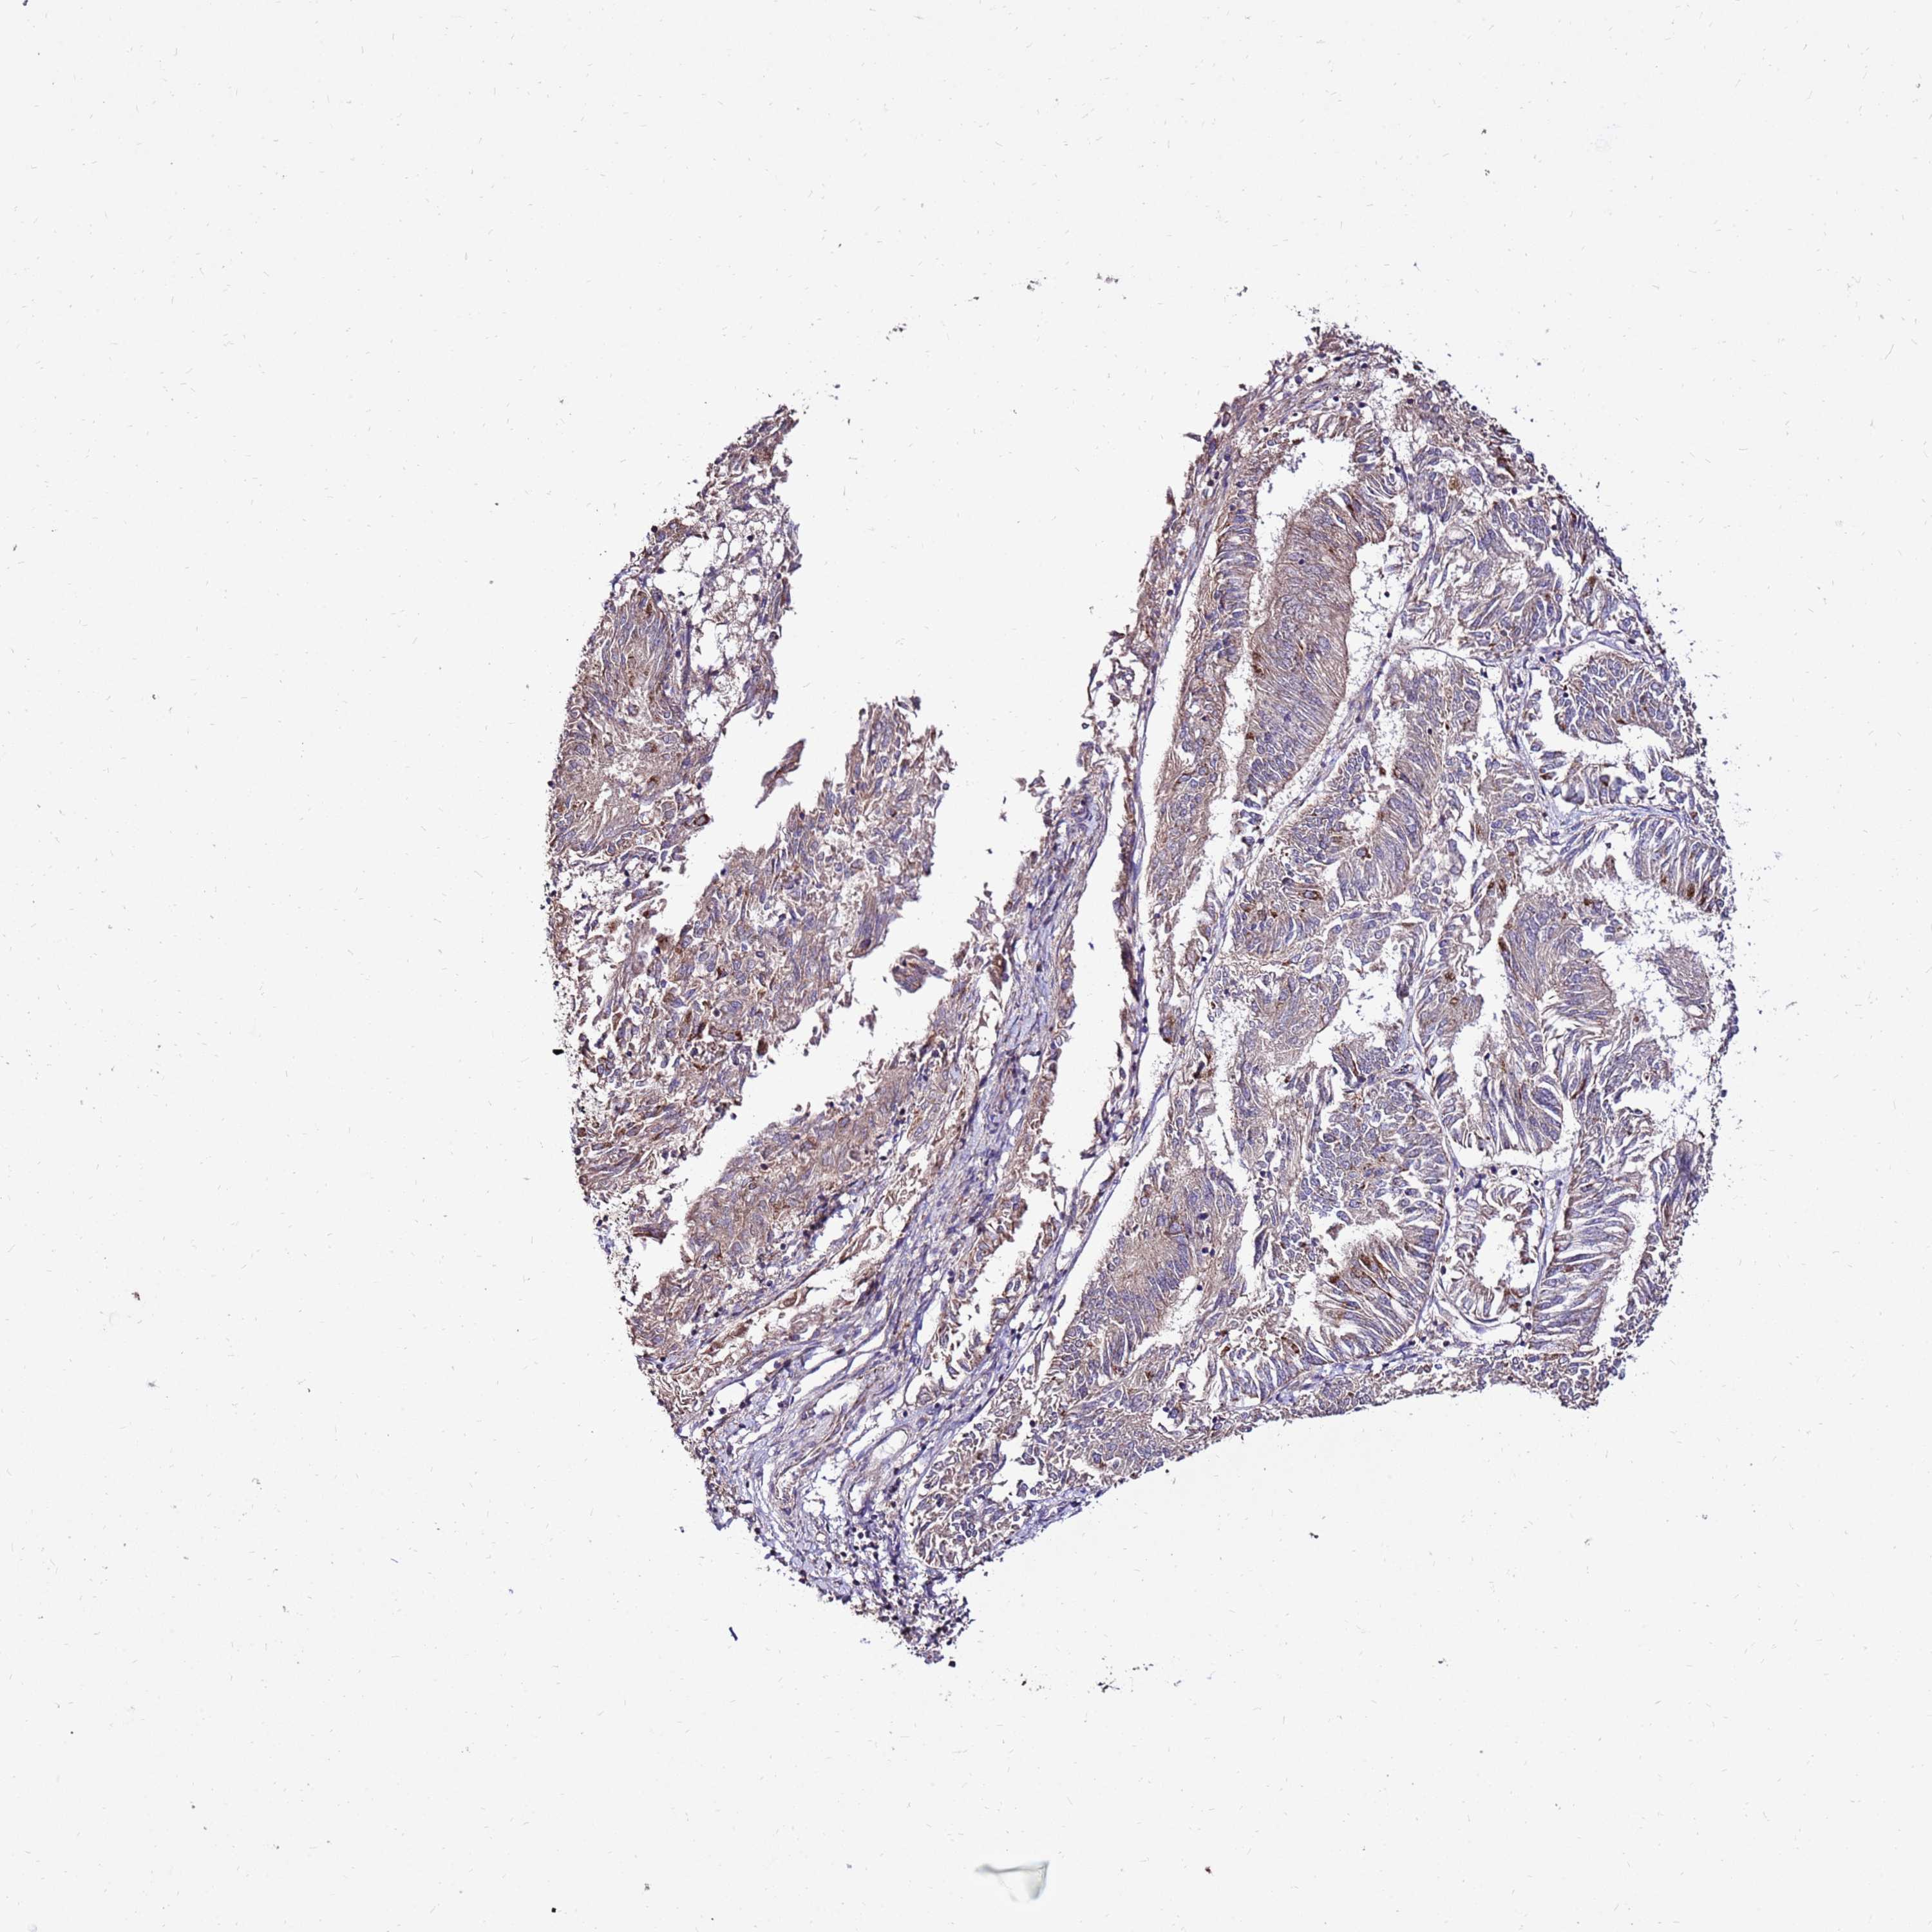

ENDOMETRIAL CANCER - Protein expressioni

A mouse-over function shows sample information and annotation data. Click on an image to view it in a full screen mode. Samples can be filtered based on level of antibody staining by selecting one or several of the following categories: high, medium, low and not detected. The assay and annotation is described here.

Note that samples used for immunohistochemistry by the Human Protein Atlas do not correspond to samples in the TCGA dataset.

Antibody stainingi

Antibody staining in the annotated cell types in the current human tissue is reported as not detected, low, medium, or high, based on conventional immunohistochemistry profiling in selected tissues. This score is based on the combination of the staining intensity and fraction of stained cells.

Each image is clickable and will lead to virtual microscopy that enables deeper exploration of all samples and also displays staining intensity scores, fraction scores and subcellular localization as well as patient and tissue information for each sample.

Antibody HPA046602

Staining

High

Medium

Low

Not detected

Intensity

Strong

Moderate

Weak

Negative

Quantity

>75%

75%-25%

<25%

None

Location

Nuclear

Cytoplasmic/membranous

Cytoplasmic/membranous,nuclear

Adenocarcinoma, NOS